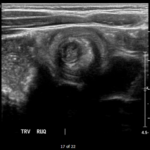

The patient’s abdominal ultrasound revealed intussusception in the right upper abdominal quadrant. The transverse ultrasound view showed a “doughnut sign” (dashed yellow line), telescoping bowel (yellow arrow), and invaginated hyperechoic mesenteric fat with crescent configuration (dashed orange line). The sagittal ultrasound view demonstrated the intussusception formed by the outer recipient bowel loop (yellow arrows), invaginated hyperechoic mesenteric fat (orange asterisks), and telescoping bowel centrally (red arrow).

Ultrasonography should be the initial imaging modality in cases with clinical suspicion for intussusception.4 Previously, contrast enemas were often used as a diagnostic tool and treatment modality. Studies have demonstrated that the modality choice had been related to age, with infants less than six months more likely to undergo enema while children greater than four were more likely to have a computed tomography scan or ultrasound.5 In the pediatric population, ultrasound has a sensitivity of 97.9% and specificity of 97.8% for diagnosis of ileocolic intussusception.6 A “doughnut,” “pseudokidney,” or “target sign” are diagnostic findings.3,7 The study could be performed by radiology or at the bedside in the ED.8,9 A study reported that with limited training, ED physicians could accurately perform ultrasound to diagnose intussusception, with a sensitivity of 85% and a specificity of 97%. Further studies are needed to determine the utility of bedside ultrasound for the diagnosis of intussusception in the community setting.3